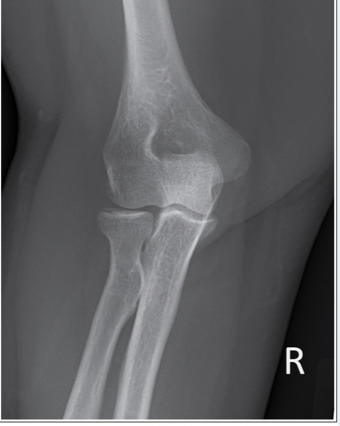

This AP elbow image demonstrates incorrect positioning of the part. What error occurred?

a.Forearm is not fully extended

b.Forearm is hyperextended

c.Humeral epicondyles are not perpendicular to the IR

d.Humeral epicondyles are not parallel to the IR

A